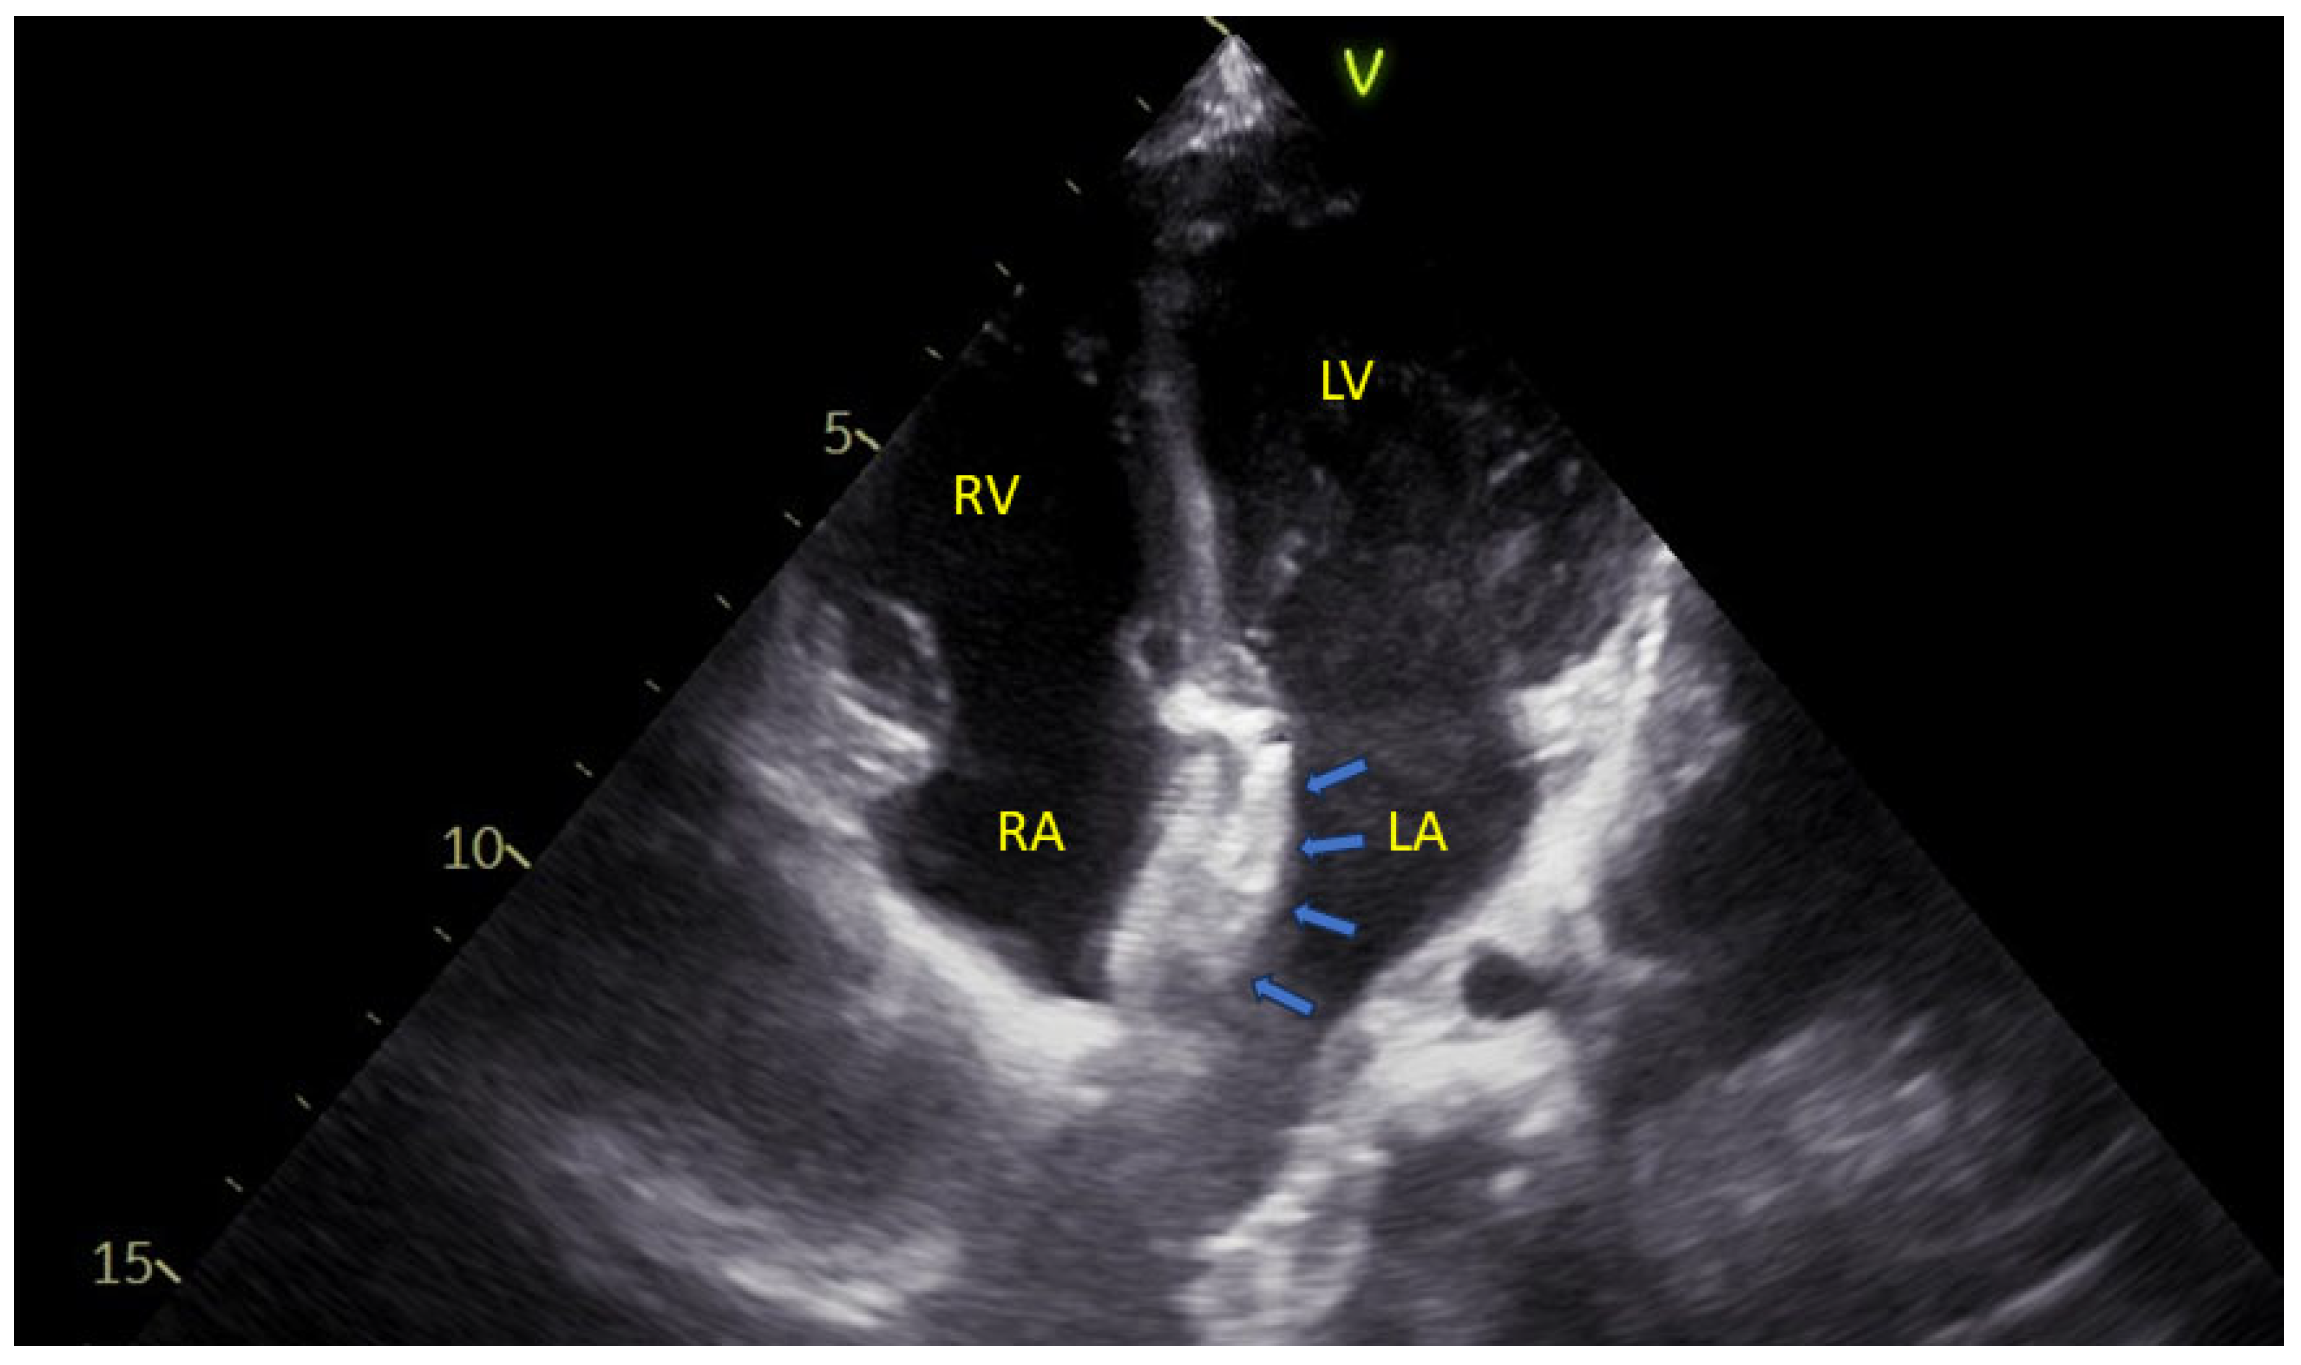

Given the natural history of hemodynamically significant atrial septal defects, international guidelines recommend closure either via percutaneous devices (as illustrated in Figure 3) or through surgical means [68,69].

Figure 3. Photographic images of an atrial septal defect closure device, showing its wireframe configuration, consisting of two round disks connected by a narrow waist. Each disk is positioned on opposite sides of the interatrial septum, with the narrow waist traversing the interatrial communication.

In the choice between these approaches, several factors are considered, such as the type of atrial septal defect (percutaneous closure is indicated only for the secundum type), the size of the opening and the dimension of the interatrial rims [70].